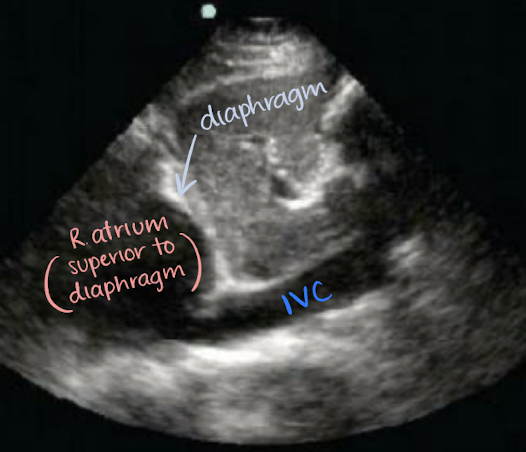

where does the IVC originate from?

common iliac veins

where does the IVC drain into?

right atrium

location of IVC

retroperitoneal

travels superiorly from the convergence of common iliac veins

to right of spine and AO

posterior to portal vein, intestine, liver

medial to RK